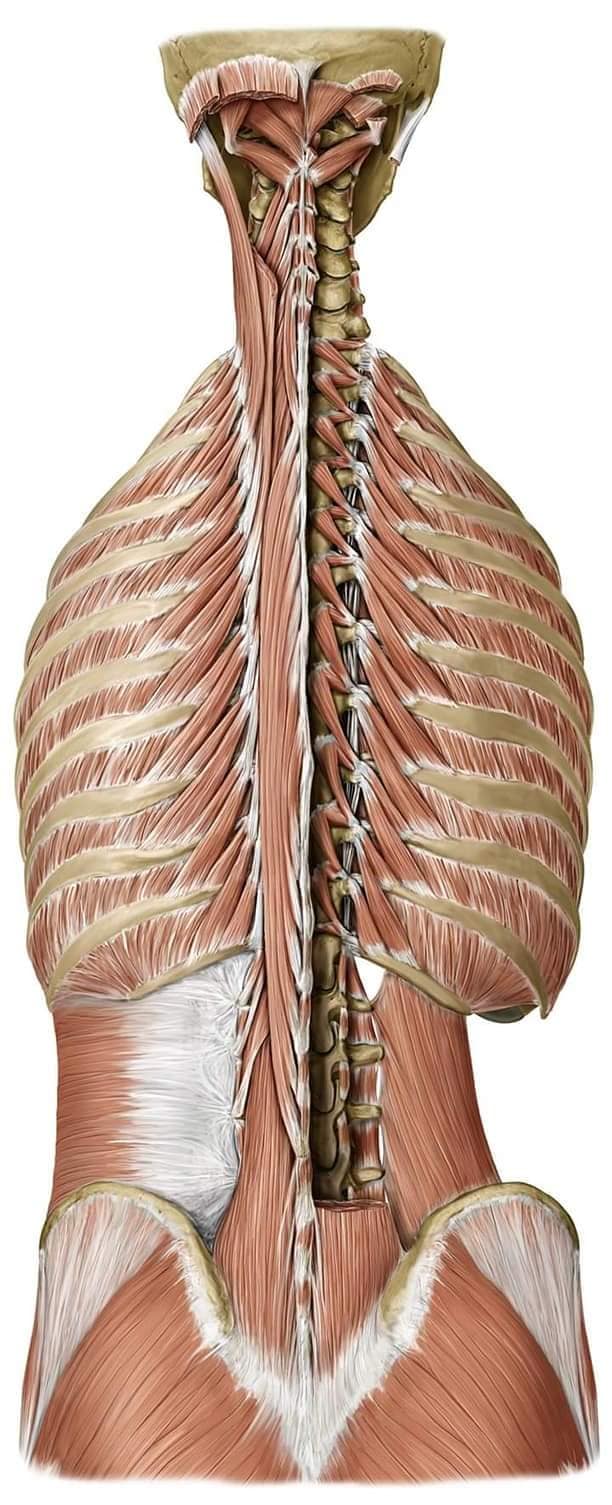

Спинні м'язи

Спинні м'язи виконують функції підтримки хребта, а також дозволяють здійснювати рухи тулуба.

Поверхневі спинні м'язи

М'язи, що піднімають лопатку: Трапецієподібний м'яз: великий м'яз, що покриває верхню частину спини. Його функція - підтримка і рух лопаток, а також забезпечення стабільності хребта.

Глибинні спинні м'язи

М'язи, що забезпечують стабільність хребта: М'язи, що розташовані між хребцями: включають мускулатуру, яка забезпечує стабільність і підтримку хребта, а також дозволяє здійснювати рухи хребта.

М'язи, що здійснюють ротацію та нахили

М'язи, що забезпечують ротацію хребта: Ротаційні м'язи: допомагають у здійсненні обертальних рухів тулуба, а також у підтримці рівноваги і стабільності хребта.